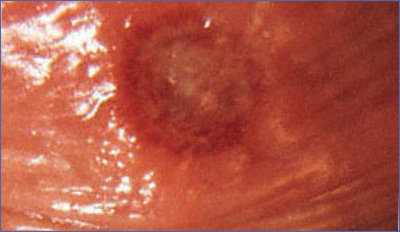

Trepenoma pallidum denen bir etken tarafından oluşturulan bir hastalıktır. Cilt belirtileri 3 safhada görülür. Nadiren doğum sırasında yada kan transferi ile gelişebilse de asıl bulaşma yolu cinsel ilişkidir. Primer Şankr: Cinsel ilişkiden yaklaşık 3 hafta sonra ağrısız ülsere düğme şeklinde bir kabarıklık gelişir. Bu lezyon genellikle temas yeri olan genital bölgededir. Ancak bazen oral ya da anal bölgede de olabilir. Bölgesel lenf bezleri büyümüştür. Eğer tedavi edilmezse de 6 hafta içinde bu safha kendiliğinden geçer. Kan tetkikleri 4.haftaya kadar temizdir. Ancak yaradan (şankr) alınan örneklerde bakteri görülebilir. İkinci safha: ilk yaranın çıkmasından 4-12 hafta sonra başlar. Gövde kol ve bacaklarda, avuç içleri ve ayak tabanlarında ufak pembe bakır renkli kaşıntısız çok sayıda ufak kabarcıklar bazen güve yeniği gibi saç dökülmesi oluşur. Ama çok farklı şekillerde lezyon oluşturabilir. Genital bölgede siğil şeklinde ya da kabarcık şeklinde lezyonlar fark edilebilir. Tedavi edilmez ise 1-3 ayda kaybolur. Kan testleri (RPR,TPHA,VDRL)pozitiftir. Üçüncü safha:(tersiyer safha) Genellikle yıllar süren belirtisiz gizli bir dönem sonrası tedavi edilmemiş sfiliz hastalarının %40'ında geç lezyonlar gelişir. Yüzde ve sırtta bazen kabuklanmalarla birlikte görülen yuvarlak şekilli ağrısız nodüller. Deri altında granulamatöz gom denen lezyonların oluşturduğu, yüzde boyunda ve baldır bölgelerinde yaralar ve yara izlerinden oluşan bir görüntü vardır. Ancak asla tam olarak iyileşmezler. Kalp ve damar sistemi ve sinir sistemi de tutulmuş olabilir. Birinci ve ikinci safhada hastalık, 10 gün süre ile procain penisilin veya tek doz 2,4 milyon ünite benzatin penisiln tek doz verilerek tedavi edilir. Penisilin alerjisi varsa tetrasiklin, doksisiklin, seftriakson yada ertromisin kullanılabilir. Hasta diğer genital yolla bulaşan hastalıklar yönünden değerlendirilmeli ve yakından izlenmelidir.2 yıl süre ile 6 ayda bir serolojik testleri ölçülür